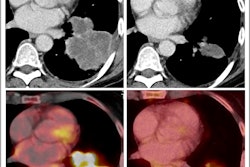

PET/CT imaging using gallium-68 (Ga-68) Fibroblast activation protein inhibitor (FAPI) radiotracer over F-18 FDG appears promising in women with invasive lobular carcinoma (ILC), according to a study published on 14 March in the Journal of Nuclear Medicine.

In an analysis of women diagnosed with ILC who underwent both imaging approaches, Ga-68 FAPI showed higher activity in tumors than F-18 FDG and identified more metastatic lesions, noted nuclear medicine physician and lead author Ertan Sahin, MD, of Gaziantep University in Gaziantep, Turkey.

An analysis by two experienced nuclear medicine physicians revealed that Ga-68 FAPI-PET/CT outperformed F-18 FDG-PET/CT, with higher radiotracer uptake in primary tumors (p = 0.001). Moreover, Ga-68 FAPI-PET/CT scans revealed more metastatic cancer in axillary lymph nodes and identified more lesions, including bone and liver metastases, according to the results.

The authors noted that F-18 FDG-PET/CT remains a highly valuable tool. Both approaches identified an identical number of primary breast lesions. Nonetheless, more accurate staging of patients with ILC may improve how they are treated, as current imaging approaches have higher rates of false negatives, they wrote.

“This study underscores Ga-68 FAPI-PET/CT’s superiority over F-18 FDG-PET/CT for ILC,” the group concluded.